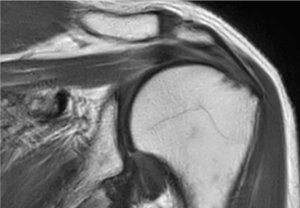

SmartSpeed は、空間分解能を最大 65% 向上させることができます¹。これにより、画像診断の精度を向上させるための情報を提供できます。

AI ベースの Philips SmartSpeed 再構成は、高速化技術の新たなベンチマークとなっています。この技術により Compressed SENSE があらゆる面で向上し、優れた画質と診断精度を維持しながらスキャン時間を短縮できます。"

Philips SmartSpeed には優れたノイズ除去機能が搭載されており、スキャン時間を延長することなく、非常に高分解能のイメージングを実現できます。これは、血管系の小さな病変を描出する場合などに非常に重要です。"